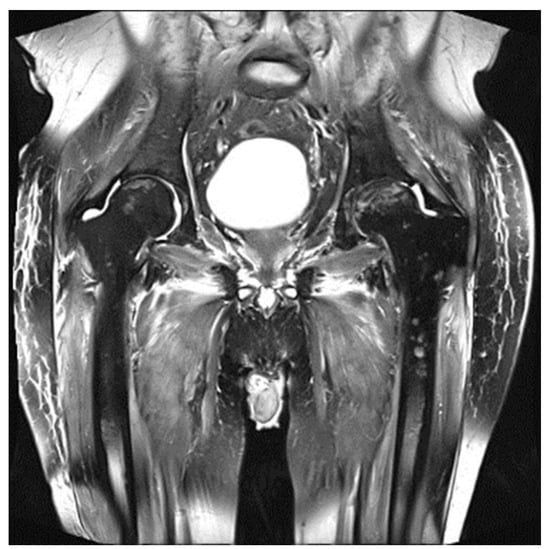

3. Value and Limits of MRI in Multiple Myeloma in the Post-Treatment Setting